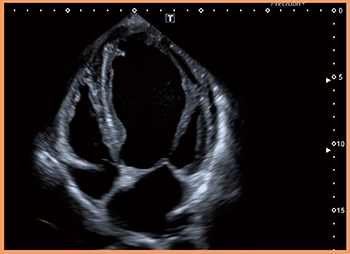

PSI-30BXは,高感度,広帯域,高スライス分解能を実現するとともに,iDMS技術により均一かつ高精細な画像を提供できるプローブである(図1)。また,経胸壁からのアプローチに合わせて最適化された先端形状と,操作性に優れたグリップ形状である。

図1 PSI-30BXによる心尖部四腔像

(画像ご提供:杏林大学・坂田好美先生)